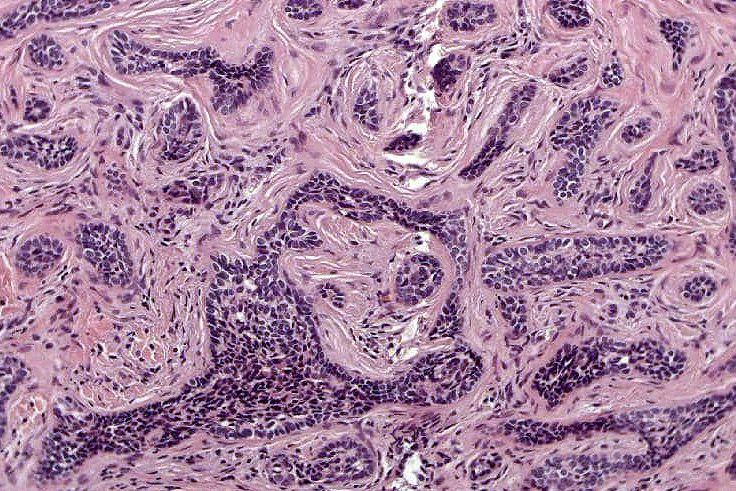

•Dermal nodule, rarely extends into subcutaneous fat

•Irregular lobules of epithelial cells embedded in a dense fibrous stroma

•Peripheral rim of darkly staining basaloid cells surrounding larger pale staining cells with vesicular nuclei with often prominent eosinophilic nucleoli

•Admixed lymphocytes (an obligatory feature)

•Germinal centers sometimes present